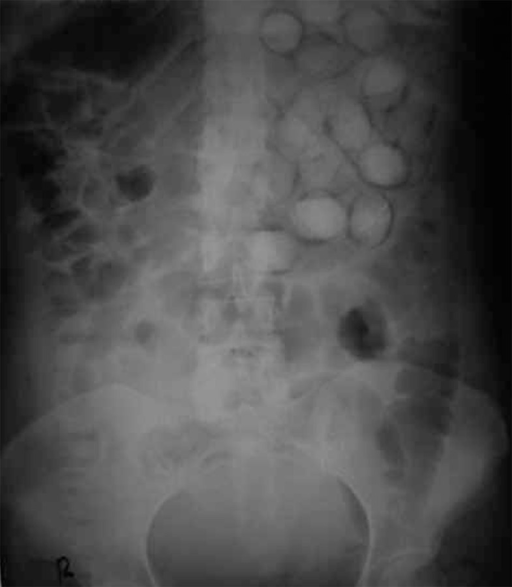

Shahnazi M, Sanei taheri M, Pourghorban R. Body packing and its radiologic manifestations: a review article. Iran J Radiol. 2011;8(4):205-10.